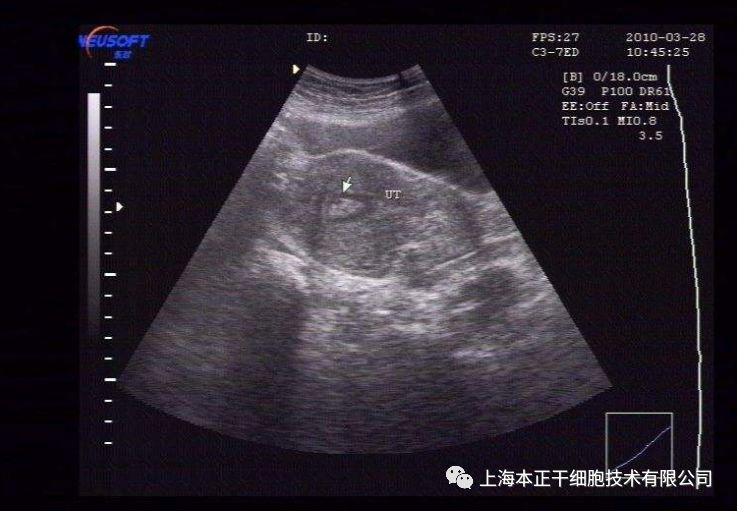

干细胞治疗方案:对患者刮宫后,在产生引导下用注射器经宫底及宫腔内注射入患者干细胞悬液,术后辅以阿司匹林和周期性激素治疗。超声检查结果显示患者术后子宫内膜再生较好,并且,患者通过体外受精(in vitro fertilization,IVF)成功怀孕,随访至妊娠第八周胎儿生长良好。

图5:胚胎移植后孕囊、卵黄囊、胚胎极及β-HCG阳性试验

图6:可见胚胎有心脏活动

图7:3D扫描8周的胎儿